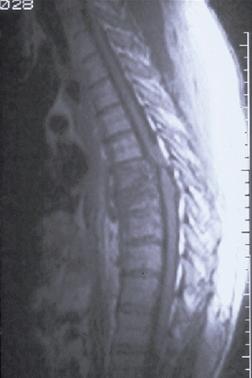

Explozie de Rinichi Fractura de coloana vertebrala T7-T8 cu

Piesa pentru examen morfopatologic compresie

medulara